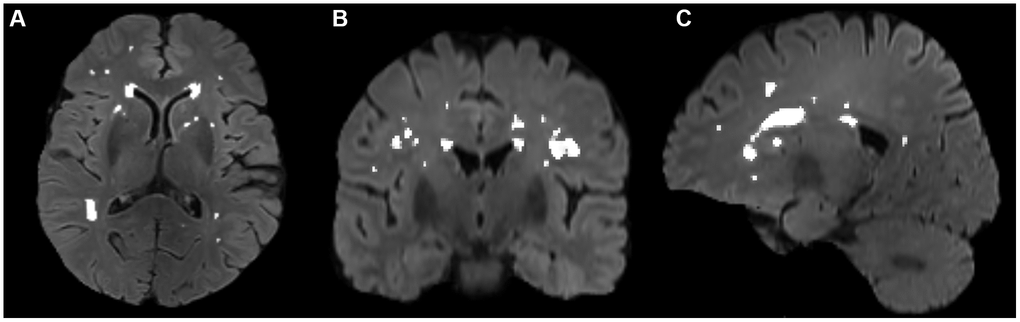

The volumes of white matter hyperintensities were derived with FSL’s Brain Intensity AbNormality Classification Algorithm (BIANCA) [54] following the UK Biobank image processing pipeline [50] and FMRIB’s Automated Segmentation Tool (FAST) [55]. The main procedures included: (a) generating a white matter mask with FAST, (b) generating a WMH mask with BIANCA in T1 space using a threshold of 0.8, which has achieved good segmentation performance according to visual check by an experienced neuro radiologist Dr. Wang, and (c) filtering non-WM voxels in the WMH mask with the white matter mask. Then, segmentation for every patient was manually checked and revised with ITK-SNAP (http://www.itksnap.org/) by Dr. Zhu. A representative segmentation of WMH volume is shown in Figure 3.

Figure 3. Segmentation of WMH volumes in the transverse (A), coronal (B), and sagittal (C) positions on FLAIR images. The white color represents the automatically segmented WMH range. WMH, white matter hyperintensities.